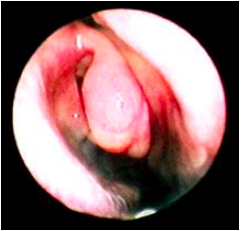

Vách ngăn là bộ phận nằm trong hốc mũi và chia đôi hốc mũi, nó được cấu tạo gồm phần sụn, xương, có chiều dài độ 8 cm, đi từ tiền đình mũi đến vòm mũi họng.

Bị vẹo vách ngăn một bên thường làm cho người bệnh bị nghẹt mũi cùng với bên vách ngăn vẹo (vẹo hình chữ C). Tình trạng nghẹt mũi này thường xuyên diễn ra, nhưng do người bệnh đã ‘quen’ dần với cảm giác này nên không để ý, nhưng nếu lấy ngón tay bịt một bên mũi, còn lại bên mũi phía vách ngăn vẹo thì mới thấy rõ tình trạng mũi không thông. Nếu bị vẹo vách ngăn cả hai bên (vẹo hình chữ S), sẽ gây nghẹt mũi cả hai bên, biểu hiện bệnh cũng không rõ lắm trong giai đoạn mũi bình thường, không bị viêm nhiễm.